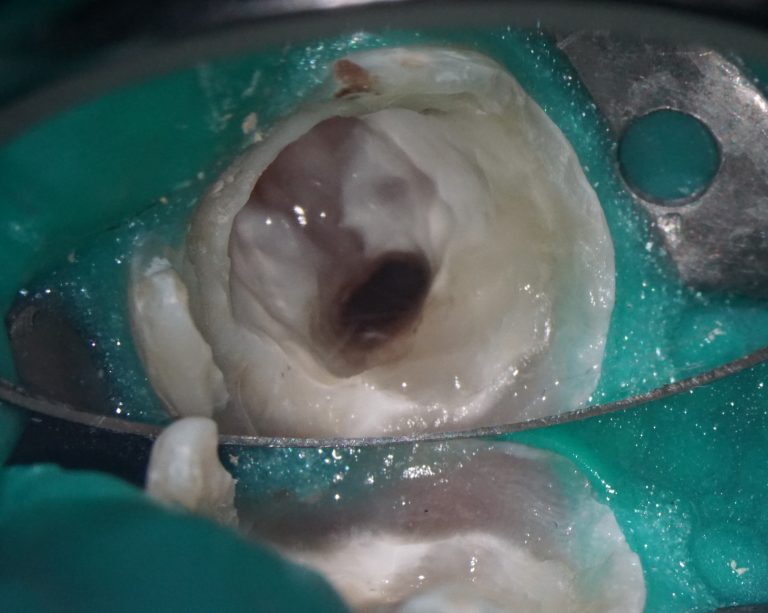

During the clinical examination, the presence of caries on the mesial surface of tooth 22 (Universal 10) has been confirmed

The presence of caries on the distal and mesial surfaces of tooth 47 (Universal 31) has been clinically confirmed